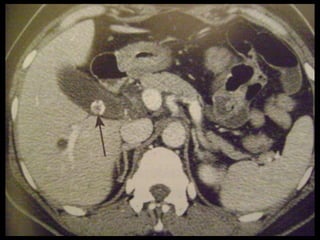

Colecistite Xantogranulomatosa

Na TC:

Os cálculos biliares e o espessamento irregular

semelhante a uma massa da parede da VB são as

anormalidades mais comuns.

Vários estudos relataram que os nódulos

hipoatenuantes intramurais vistos na TC

representam uma lesão xantogranulomatosa, um

abscesso ou a combinação de ambos;

Realce da superfície luminal(70%) correspondia à

presença de uma camada epitelial.

Colecistite Xantogranulomatosa Na TC: Os cálculos biliares e o espessamento irregular semelhante a uma massa da parede da VB são as anormalidades mais comuns. Vários estudos relataram que os nódulos hipoatenuantes intramurais vistos na TC representam uma lesão xantogranulomatosa, um abscesso ou a combinação de ambos; Realce da superfície luminal(70%) correspondia à presença de uma camada epitelial.